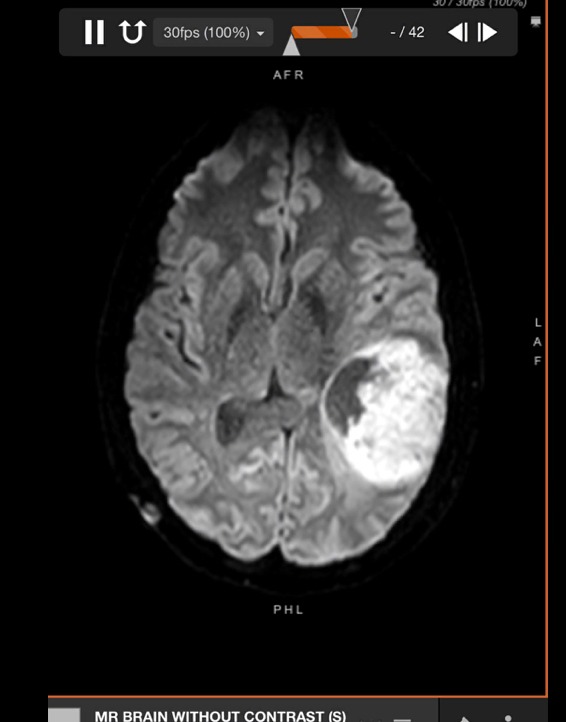

On February 24, 2025, not even a week after Nick’s 24th birthday, he went to the ER with debilitating pressure in his head, dizziness and tunnel vision. Imaging and lab results indicated the need for a higher level of care; therefore, he was transported to CRMC, a level 1 trauma center. Nick was admitted to the Neuro ICU and awaited surgery to remove a large 8cmx5cmx5cm brain tumor. We feel blessed that the surgeon was able to successfully resect the entire tumor, but soon after, we received the devastating news that the tumor was malignant. Nick was diagnosed with a rare aggressive and incurable brain cancer. Pathology results determined the tumor to be a very rare grade 4 pediatric high-grade glioma, H3 and IDH wildtype with NF1 and MMR mutations. These tumor cells are resistant to standard treatment.

Nick has several stable benign tumors related to NF, which is why he regularly had MRIs. However, this brain tumor was new and different from the rest which was not on his scans 18 months ago.